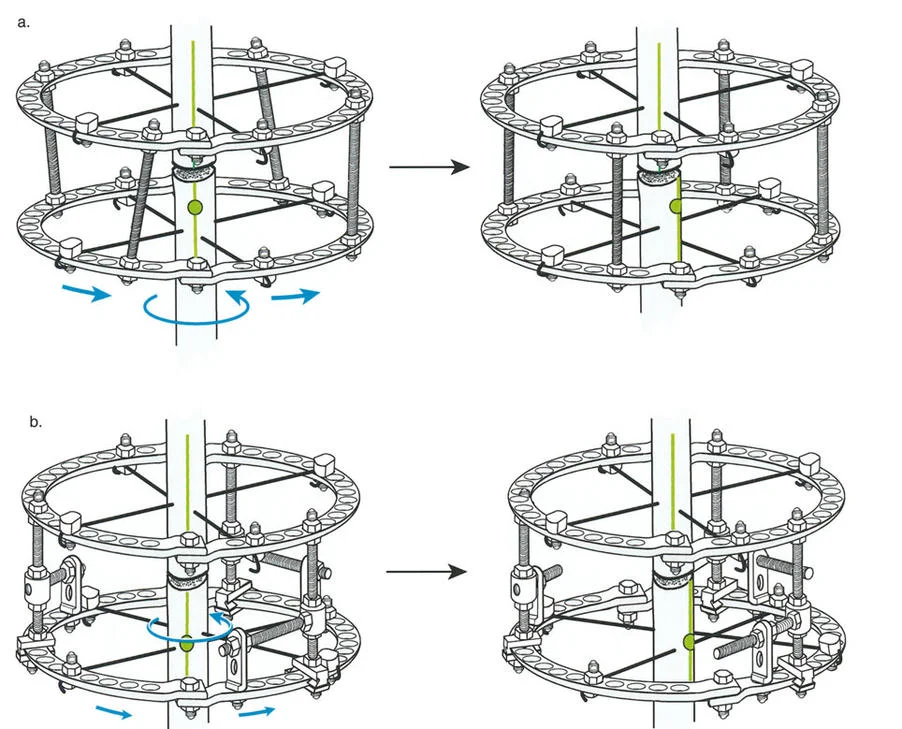

- مثبتات إليزاروف الدائرية الكلاسيكية: تتكون من حلقات معدنية متصلة بالعظم بأسلاك رفيعة، وتسمح بتصحيح متعدد المستويات.

المفصلات القريبة من المفصل وقواعد قطع العظم (Osteotomy Rules)

عند التعامل مع التشوهات الواقعة بالقرب من خط المفصل - مثل التقوس الشديد في الجزء العلوي من الساق (مرض بلونت) أو التشوه الفحجي في الجزء السفلي من عظم الفخذ - يصبح وضع الجهاز مقيدًا هندسيًا. إن المتطلبات البيولوجية للحفاظ على كبسولة المفصل، وتجنب وضع الأسلاك داخل المفصل، ومنع التهاب المفاصل القيحي، غالبًا ما تجبر الجراح على وضع الحلقة المرجعية على مستوى مختلف تمامًا عن مركز دوران الانحراف (CORA) الفعلي.

تحدي مركز دوران الانحراف (CORA) القريب من المفصل

لمطابقة مفصلة المثبت الخارجي مع المستوى الدقيق لمركز دوران الانحراف (CORA)، يجب غالبًا بناء المفصلة فوق أو تحت مستوى الحلقة الفعلية. يُعرف هذا في مبادئ بالي باسم تجميع المفصلة القريبة من المفصل (juxta-articular hinge assembly).

إذا كان مركز دوران الانحراف (CORA) يقع بالقرب من خط المفصل، فإن وضع حلقة إليزاروف القياسية عند هذا المستوى بالضبط مستحيل دون انتهاك مساحة المفصل أو شد الهياكل الكبسولية الحيوية. لذلك، يتم تثبيت الحلقة المرجعية بالعظم الكثيف أو العظم الطويل المتاح، ويتم بناء آلية المفصلة باستخدام قضبان ملولبة، ولوحات توصيل، ودعامات. ثم يتم "إنزالها" (أو رفعها) لتتطابق تمامًا مع مركز دوران الانحراف (CORA) الهندسي الحقيقي.